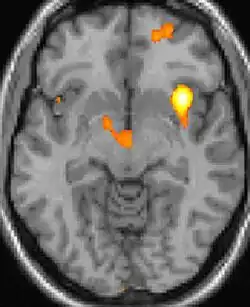

As reais causas da cefaleia em salvas (CES) ainda são desconhecidas, mas, de acordo com alguns estudos, os padrões das crises, as influências pelo horário do dia e as estações sugerem que o relógio biológico do corpo está envolvido. Nos seres humanos, o relógio biológico está situado no hipotálamo. Durante um ataque, o hipotálamo libera substâncias químicas que podem estimular as células nervosas no cérebro, causando dor e outros sintomas. A hiperatividade nervosa também pode causar um alargamento (vasodilatação) das artérias no lado afetado do cérebro. Uma teoria é que as dores são causadas por um alargamento dos vasos sanguíneos, que pressionam sobre os tecidos nervosos próximos, causando dor.[5] Exames de ressonância magnética sugerem dilatação da artéria oftálmica durante uma crise de cefaleia, enquanto a tomografia por emissão de pósitrons (PET) revela atividade dentro do seio cavernoso. Em alguns casos, existem fatores genéticos também, pois é mais comum entre familiares.[6]

![]() | ![]() | ![]() |

| Tomografia PET mostrando áreas ativadas na dor. | ||